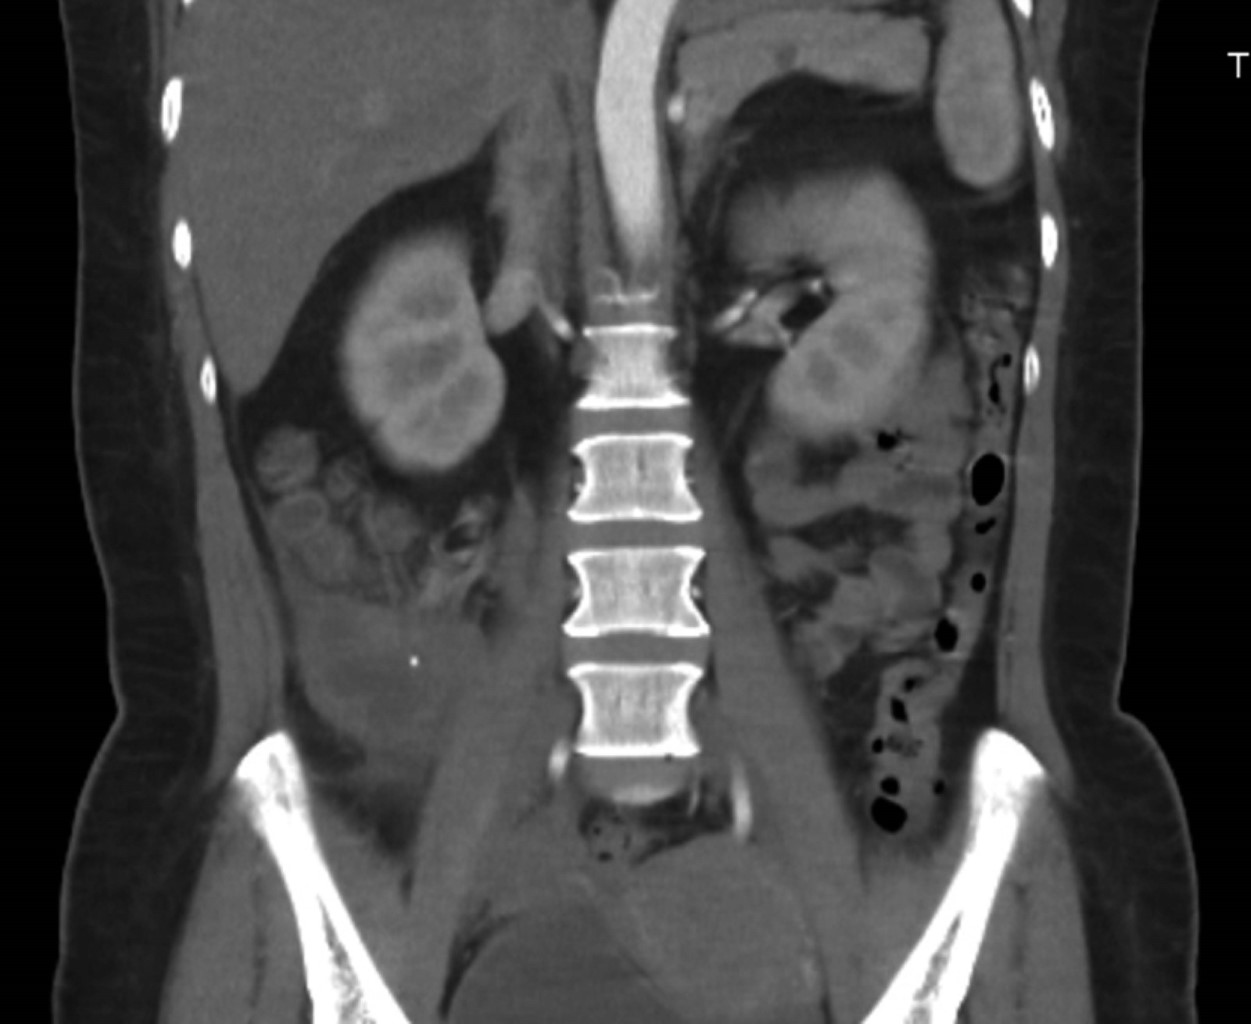

A simple and contrasted abdominopelvic CT scan on 03/11/22 showed a sub and retrocecal collection of 50 cm3 with a peripheral inflammatory process, suggesting a complicated appendicular process (Figures 1 and 2).

The literature reports a female predominance and a peak presentation between the fifth and sixth decade of life on average, as in our patient. There is no established test for diagnosis. However, in ultrasonography studies, a hypoechoic lesion can be observed, while in tomography, the images are hypodense and homogeneous, like "onion layers", sometimes with cystic areas inside or with calcified walls many times adjacent to the cecum.7 If the appendix measures ≥ 15 mm in its transverse diameter, a mucocele should be suspected with a sensitivity of 83% and specificity of 92%.8

The imaging test of choice is computed tomography, which is diagnostic in less than 50% of the cases.1 Although, in the first instance, the diagnostic suspicion in our patient was acute appendicitis and not a mucinous tumor of the appendix, computed tomography -which is considered the best imaging study in both pathologic entities- was an essential diagnostic complement in the approach; however, it was not conclusive. The irregularity in the appendiceal wall and increased soft tissue thickness may predict tumor malignancy.8

Figure 1

Figure 2